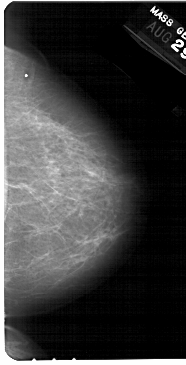

A_1347_1.LEFT_MLO

LEFT_MLO LINES 5491 PIXELS_PER_LINE 2941 BITS_PER_PIXEL 12 RESOLUTION 43.5 OVERLAY

FILE: A_1347_1.LEFT_MLO.OVERLAY

TOTAL_ABNORMALITIES 1

ABNORMALITY 1

LESION_TYPE MASS SHAPE IRREGULAR MARGINS ILL_DEFINED

ASSESSMENT 4

SUBTLETY 2

PATHOLOGY BENIGN

TOTAL_OUTLINES 1

BOUNDARY